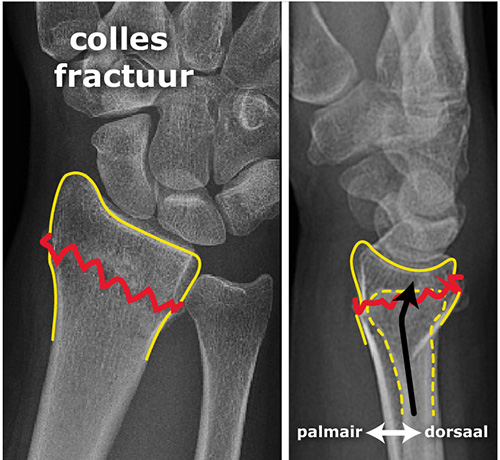

3-1: علایم شکستگی انتهای ساعد: بدنبال شکستگی مچ دست بسیار دردناک و متورم میشود. حرکات مچ محدود و همراه درد بوده، فشار به ناحیه شکسته شده موجب افزایش شدت درد میشود. در شکستگی های با جابجایی زیاد ظاهر مچ دست کاملا تغییر شکل میدهد. جابجایی قطعه شکسته شده به سمت پشت و بیرون موجب میشود تغییر شکل خاصی در ظاهر مچ دست شکسته شده ایجاد شده و به شکل چنگال درآید . گاهی اوقات جابجایی قطعه شکسته شده برعکس بوده و به سمت جلو جابجا میشود که به آن شکستگی اسمیت (Smith fracture ) می گویند.

1-4: تشخیص شکستگی انتهای ساعد: تشخیص قطعی این شکستگی با رادیوگرافی ساده است. در رادیوگرافی ساده خط شکستگی بالای سطح مفصل مچ دست دیده میشود. قطعه بین خط شکستگی و مفصل مچ دست به سمت پشت و خارج جابجا میشود. گاهی این قطعه شکسته شده خرد بوده و گاهی خط شکستگی به درون مفصل مچ هم راه پیدا میکند .